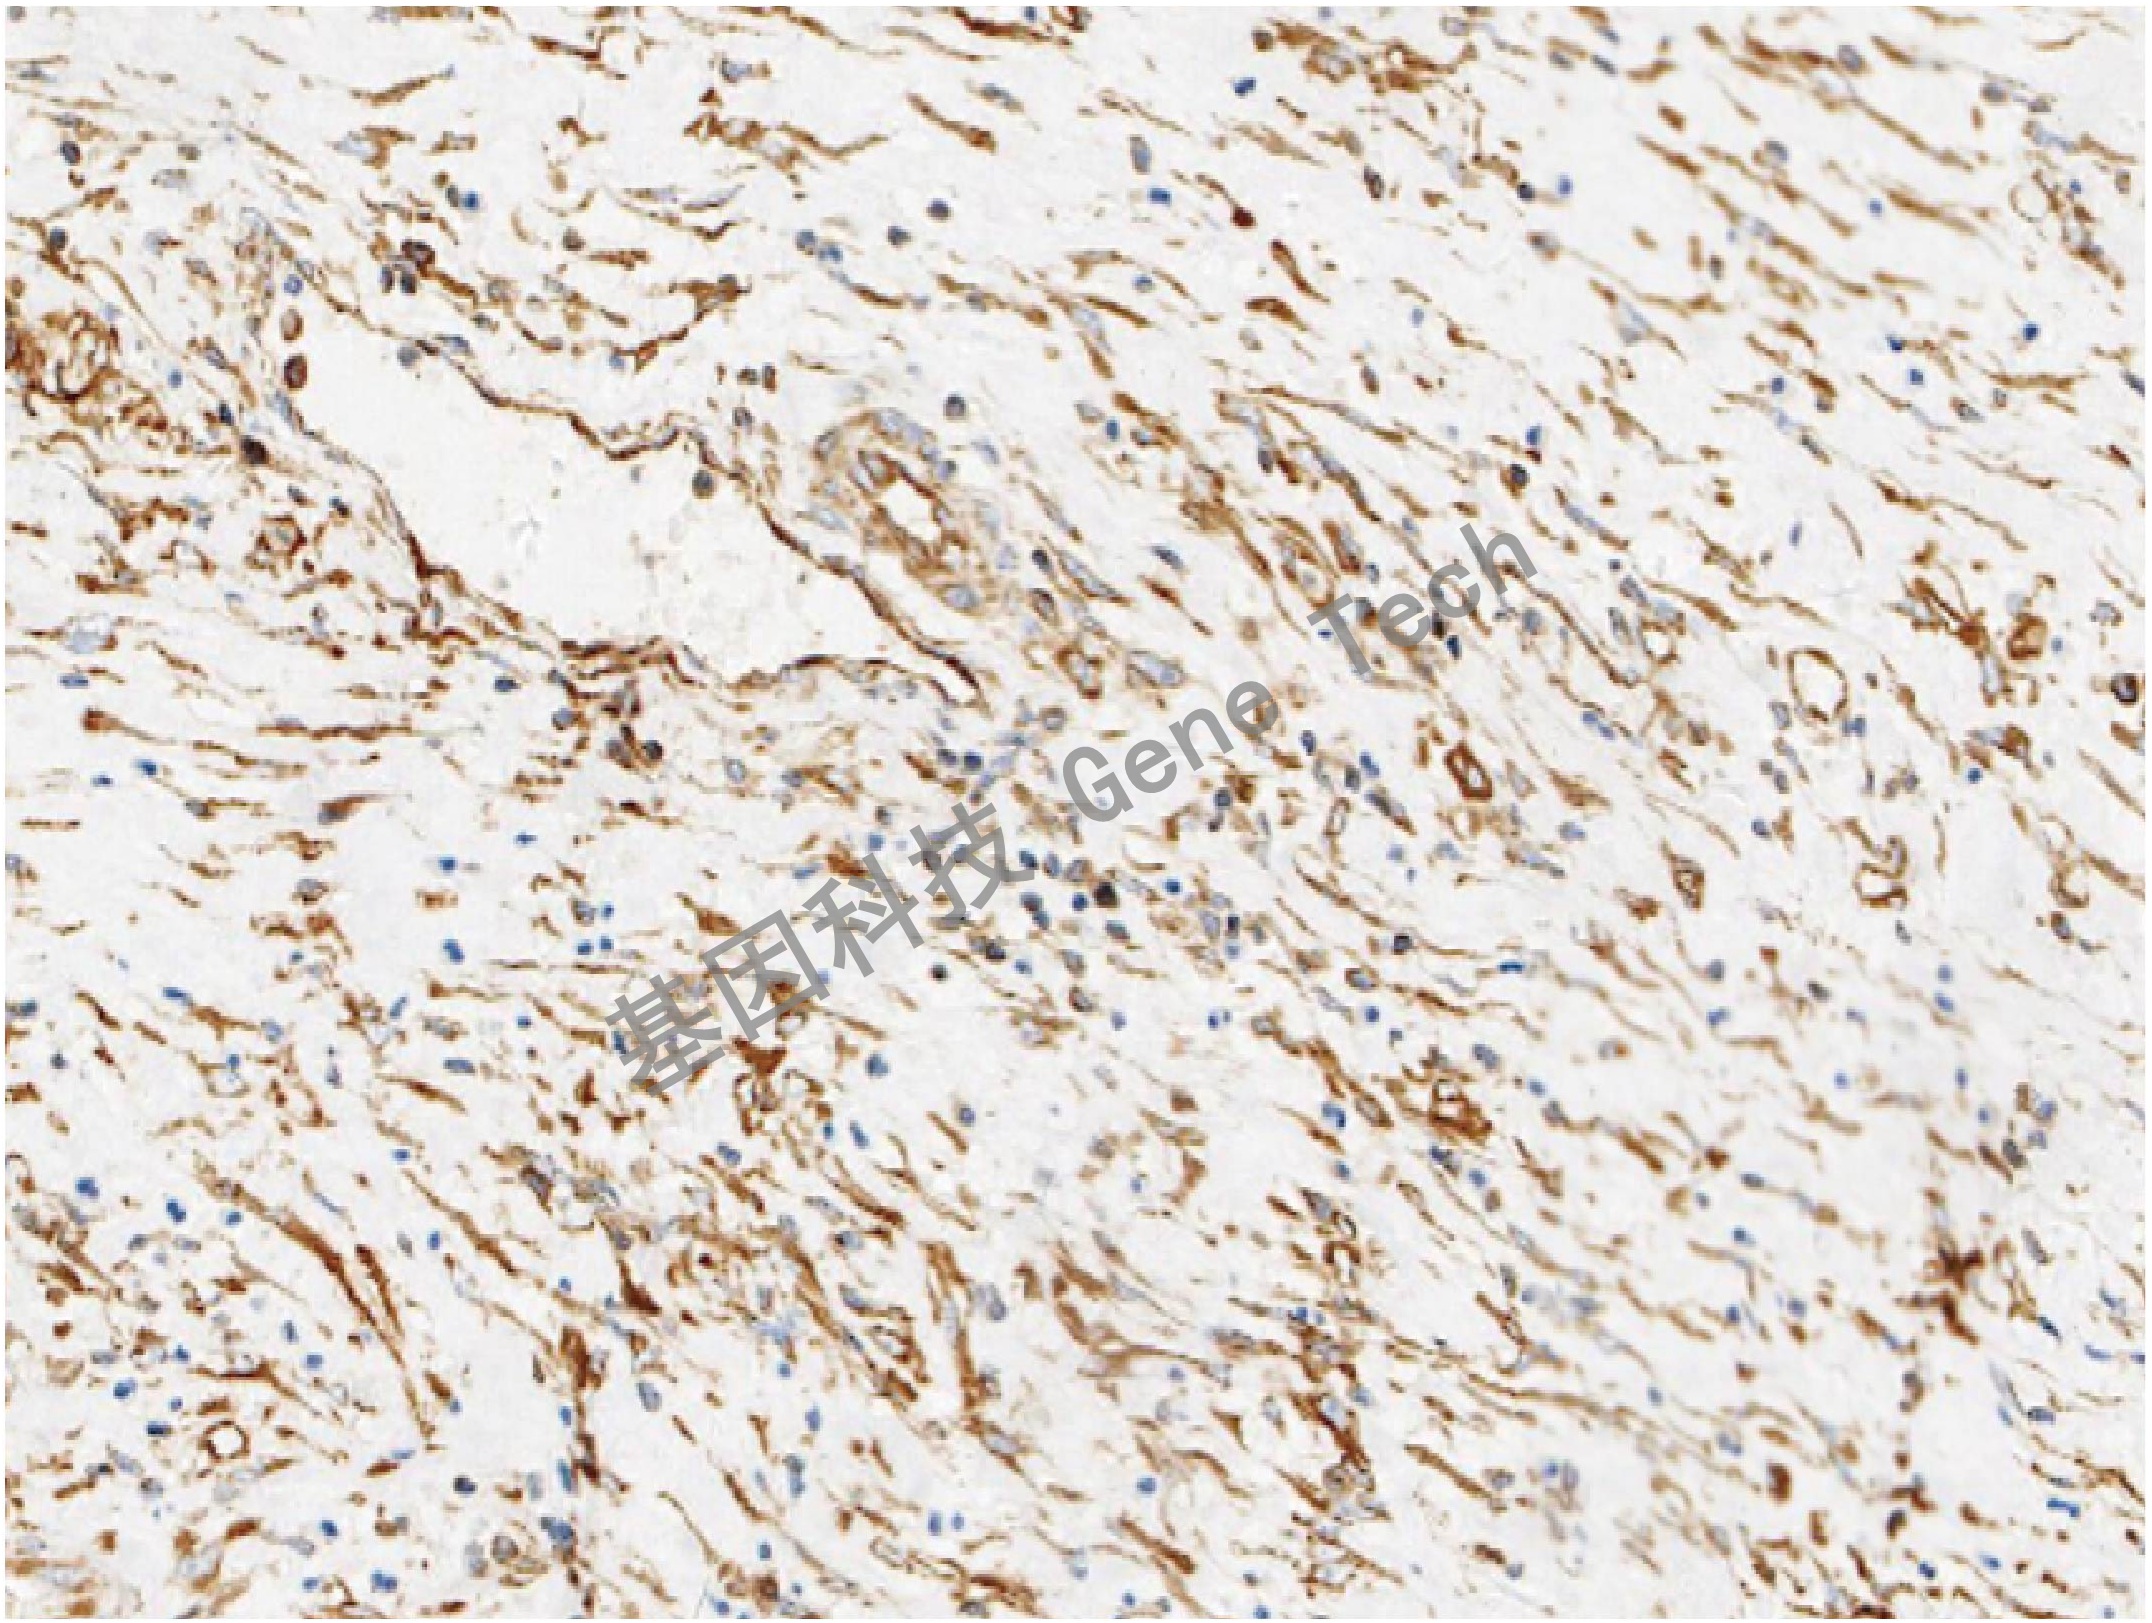

| 預處理:高pH熱修復 | 陽性部位:細胞漿 | 陽性對照:食管癌 |

| 食管癌石蠟切片,用 Tubulin β(GT2373)染色,細胞漿陽性,DAB 顯色。 | ||